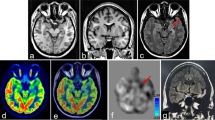

Analyses were performed by dichotomizing between patients with metabolic pattern C and those with the other metabolic patterns. The different paterns are shown in example TLE and ETLE patients in Fig. 2.

Metabolic patterns identified in temporal lobe epilepsy (TLE) and extratemporal lobe epilepsy (ETLE) in the study participants (colour bars indicate T values, individual maps are thresholded at p < 0.01, k > 40, R indicates right hemisphere, L indicates left hemisphere). The images indicate the presumed seizure onset zone (SOZ) location and the surgical outcome (Engel class) in surgically treated patients

There were no significant differences in the distribution of metabolic patterns, namely C, C+, M, R and N, between ETLE and TLE patients, nor between TLE patients with and without HS (p = 0.08 and p = 0.31, respectively). Analysis of the different hypometabolic regions in TLE patients showed that five patients had extratemporal hypometabolism in more than one area (22 hypometabolic foci in total). These were noted in the frontal, insular, parietal/temporal posterior and occipital cortex. Overall, remote hypometabolism was more frequent in the frontal lobe (12 of 22, 55%) and ipsilateral to the side of the temporal focus (18 of 22, 82%; an example is shown in Fig. 2). Among patients with HS, additional hypometabolism was observed outside the SOZ lobe in 14 of 45 patients with HS, most commonly contralateral temporal hypometabolism (7 patients). In ETLE patients, additional temporal hypometabolism was observed in 8 of 44 patients (18%), 5 of 8 (62%) ipsilateral and 3 of 8 (38%) bilateral. Temporal hypometabolism was associated with frontal epilepsy in three patients (one bilateral), with parietal epilepsy in two (one bilateral), and occipital epilepsy in three (one bilateral; Fig. 2).